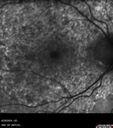

Elmiron (pentasosan polysulfate) Macular Toxicity

77 year old female who had been on Elmiron for 20 years and stopped it 2 years ago